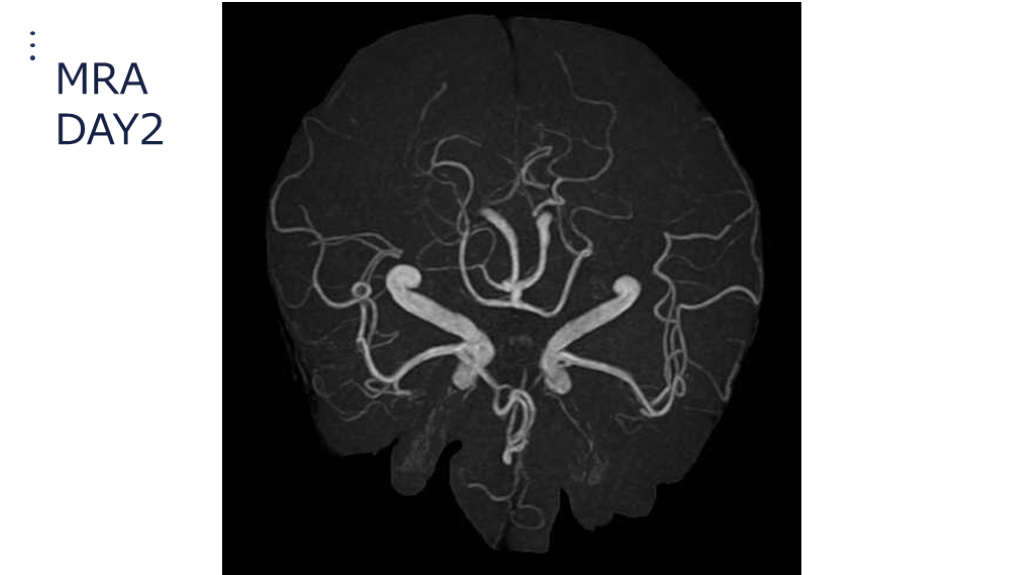

#35.

MRA DAY2